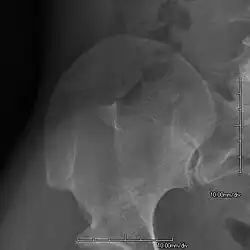

- Exostoses arising from the posterior aspect of the iliac bones ("iliac horns") are present in as many as 70-75% of patients; this finding is considered pathognomonic for the syndrome.

The hallmark features of this syndrome are poorly developed fingernails (especially of thumbs) - in approximately 95 percent of patients, rarely - toenails (especially the smallest nail of feet), and hypoplastic or aplastic patellae (kneecaps) - in approximately 75 percent of patients. Sometimes, this disease causes the affected person to have either no thumbnails or a small piece of a thumbnail on the edge of the thumb. The lack of development or complete absence of fingernails results from the loss of function mutations in the LMX1B gene. A unique feature of this syndrome is also the triangular lunulae at the base of the fingernails - especially in NPS patients who have nails present (in healthy individuals, without NPS, lunulae are semicircular).[10] This mutation may cause a reduction in dorsalising signals, which then results in the failure to normally develop dorsal specific structures such as nails and patellae.[18] Other common abnormalities include elbow deformities, kidney disease,[19] and abnormally shaped pelvic (hip) bones. Individual cases of this syndrome may be diverse and not fully symptomatic, as is the case with any genetic syndrome, they may also affect fitness and functioning of the body to varying degrees - from severe to mild cases (different mutations - pathogenic variants regarding other fragments/exons of the same gene and varying degrees of impact on the phenotype and areas of the body, even in the case of the same mutation in relatives in the same family).